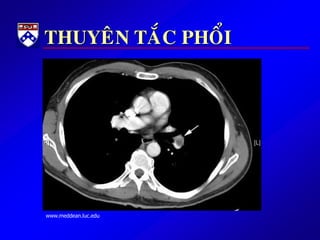

THUYEÂN TAÉC PHOÅI

 HUYEÁT KHOÁI TRONG LOØNG

TM GAÂY TAÉC ÑM PHOÅI

 HK THÖÔØNG ÔÛ CHI DÖÔÙI

HOAËC KHUNG CHAÄU

 GAÀN ½ BN TTP KHOÂNG ÑÖÔÏC

CHAÅN ÑOAÙN

 TÖÛ VONG 30% NEÁU KHOÂNG

ÑIEÀU TRÒ.

 TÆ LEÄ TÖÛ VONG GIAÛM COØN 2-

8% NEÁU ÑIEÀU TRÒ KÒP THÔØI

 Beänh söû: ÑN kieåu maøng phoåi, khôûi phaùt ñoät ngoät, khoù

thôû, quaù trình naèm laâu, coù tieàn caên huyeát khoái chi döôùi,

or ñau /söng chaân

 Khaùm: ral rít ôû phoåi, nhòp tim nhanh, huyeát aùp thaáp,

SpO2 thöôøng bình thöôøng, phuø chaân thöôøng 1 beân

 Xeùt nghieäm: D-dimer, V/Q scan, CT scan ngöïc

 Ñieàu trò:khaùng ñoâng; xeùt chæ ñònh söû duïng tieâu sôïi huyeát

or phaãu thuaät laáy huyeát khoái neáu thuyeân taéc phoåi naëng.

www.meddean.luc.edu